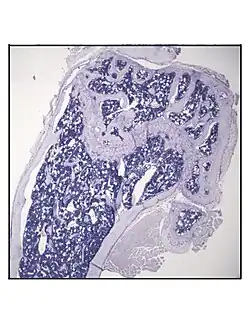

Representative distal femur histologic section of a 16-week-old healthy C57BL/6 mouse demonstrating a typical quantity of marrow adipocytes. -